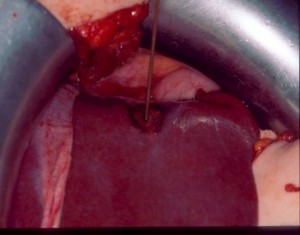

Εκτομή των ηπατικών μεταστάσεων.